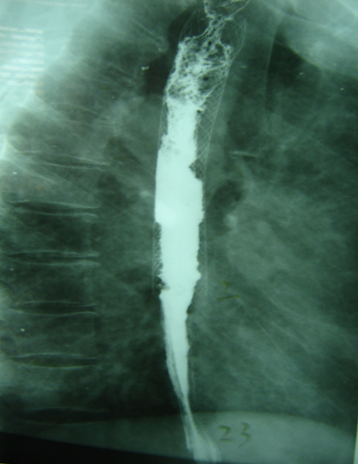

食管癌介入术后